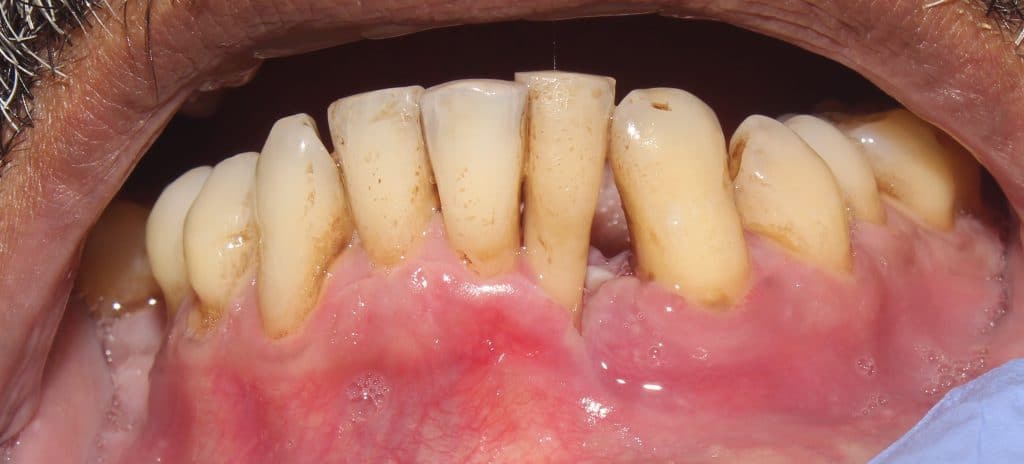

Healing at 1 week and 2 weeks in shown with characteristic recession and reduced pocket depth.

healng at 2 weeks. note the developing recession.. and reduction in pocket depths.